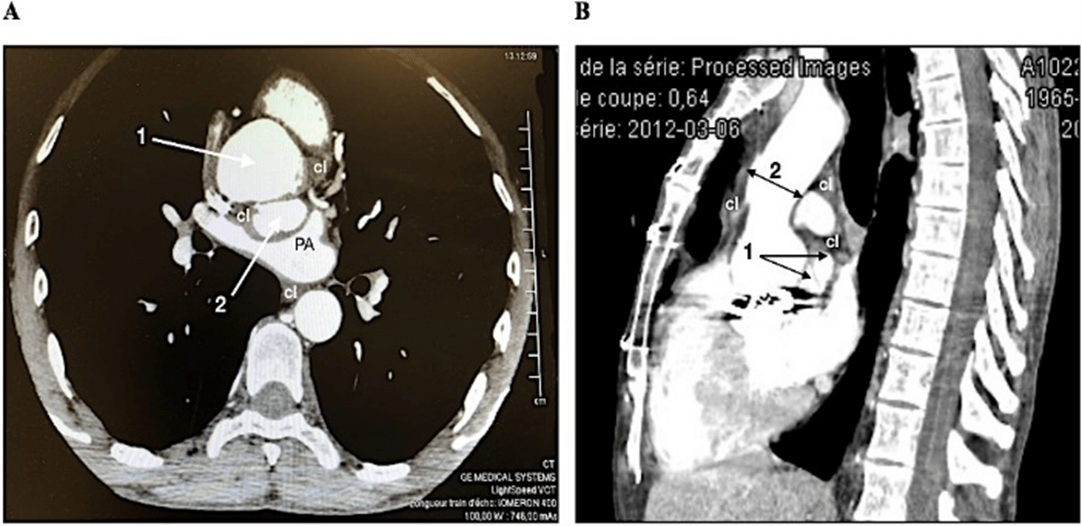

A 55-year-old male patient was referred to our institution with a diagnosis of acute aortic root dissection. On admission, clinical examination showed a severe vena cava syndrome with dyspnea. The patient was hemodynamically stable. At the age of 18, the patient had undergone aortic valve replacement with a Bjork-Shiley prosthesis. Since then, he received oral anticoagulation with acenocoumarol. On admission, the International Normalized Ratio (INR) was 4.1. CT-scan initially reported a limited dissection of the aortic root (horizontal section) with 2 lumen and a pericardial effusion and clots compressing both right atrium and superior vena cava (Figure 1A). The compression was worsened by pericardial adherences. After reexamination of the sagittal section (Figure 1B), the diagnosis of a 5cm-diameter ruptured A-NCSOV was validated. The aorta above the sinotubular junction was dilated.

Figure 1: A) CT-scan horizontal section of the aortic root showing two lumens (1 and 2) surrounded by clots (cl). B) CT-scan sagittal section showing a complete rupture of the NCSOV (1) with clots (cl). The aorta is dilated (2).